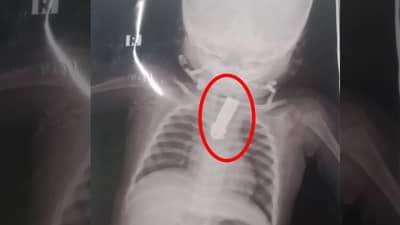

नाशिकमध्ये आठ महिन्याच्या मुलाने चक्क नेलकटरच गिळलं होतं. नाशिक रोडच्या के जी मेहता या परिसरात सोमवारी ही घटना घडली. लहानग्याची तब्बेत बिघडली म्हणून त्याचे आईवडील त्याला डॉक्टरांकडे घेऊन गेले. डॉक्टरांनी मुलाचा एक्सरे रिपोर्ट काढला. हा रिपोर्ट पाहून डॉक्टरही बुचकळ्यात पडले. चिमुकल्याच्या गळ्यात नेलकटर अडकल्याचं रिपोर्टमध्ये दिसून आलं होतं.

साधरण काल रात्री कॅज्युलिटीमधून डॉक्टरांना इमर्जन्सी फोन आला. या चिमुकल्या बाळाचं नाव आशिष होतं. मेडिकल कॉलेजमधील डॉ. हेमंत आणि एनेस्थेशिया टीमने ऑपरेशनला सुरुवात केली. पुढच्या दातांपासून 22 सेंटीमीटर अंतरावर असलेलं हे नेलकटर अडकलं होतं. दुर्बिणीच्या साहाय्याने डॉक्टरांनी हे ऑपरेशन केलं आणि नेलकटर बाहेर काढलं, अशी माहिती डॉक्टरांनी दिलीय.